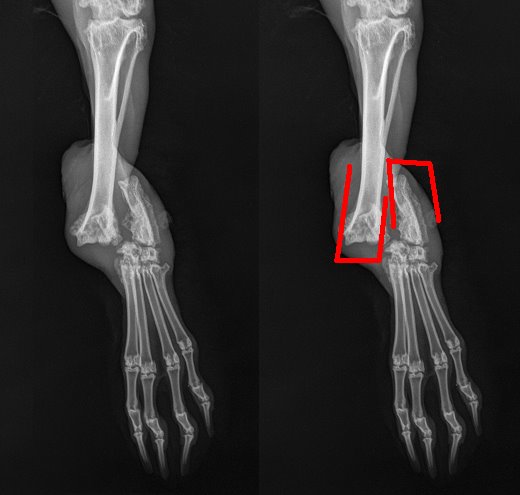

Isti dan i čim je mogla, volonterka Ivana S. ♥ ga je odvela do Zagreba u vet.amb.Buba na RTG i pregled, prije nego ga na privremenu skrb prihvati Maris ♥. Na njegovom sitnom tijelu rendgen nije ništa prikazao, ali je možebitno prisutno oštećenje moždine te zato vuče nogice...i ništa ne osjeća na njima :(( .

Volonterka Maris preuzela ga je to popodne i javila nam da je kunić u jako lošem stanju. Kralježnica mu je izričito deformirana u gornjem (torakalnom) dijelu, a na jezivim rengenskim snimkama izgleda kao da mu je k tome i slomljena kost na jednoj od nogica…